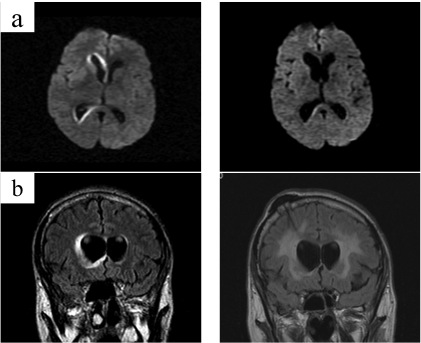

Lymphomatoid Granulomatosis of Central Nervous System and Lung Driven by Epstein Barr Virus Proliferation: Successful Treatment with Rituximab